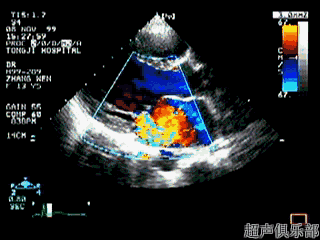

循环活动中,瓣膜扮演的角色就是心腔内的交通执法者,指挥着血液的流动

保证血液循环由右心房一定向右心室方向流动和通过一定流量